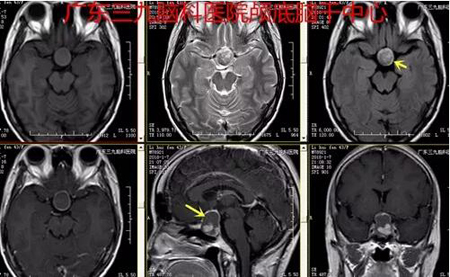

▲图3:2018-01-07术前MR示鞍内及鞍上一囊实性占位性病变,囊性部分呈短T1长T2为主异常信号影,FLAIR序列呈高信号,间杂小斑片状短T1高信号影;实性部分呈长T1偏等T2异常信号影,FLAIR序列呈偏等信号,增强扫描实性部分及囊壁呈明显强化。病变边界清,大小约为20mm×28mm×17mm,突破鞍隔向上生长,视交叉受压